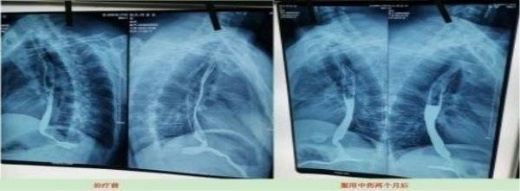

案例5、食道癌两个月清零

Case5. Oesophageal cancer was cleared for two months

患者:刘喜良 男 46岁 食道中段癌

2023年10月9日CT影响报告诊断查出食管壁增厚,管腔狭窄,食管癌。找到陈海林老师使用中医药两个月治疗后CT显示食管各段顺利通过,食管恶性肿瘤治疗后改变。

Patient: Liu Xiliang, male, 46-year-old middle-esophageal cancer On 9 October 2023, CT affected the diagnosis of food tube wall thickening, lumen stenosis, and esophageal cancer. After finding Chen Hailin for two months, CT treatment showed the smooth passage of all section of the esophagus, and the esophagus of malignant tumor changed after treatment.

上图是服用两个月中药的前后对比图

Above is a comparison of before and after taking traditional Chinese medicine for two months

上图是服用两个月中药后检查报告对比图

The figure above is a comparison diagram of the examination report after taking TCM for two months